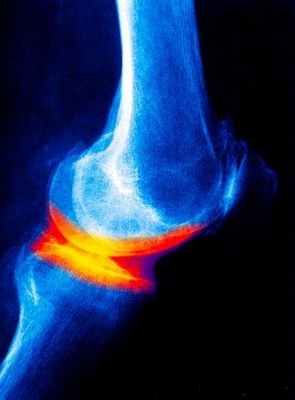

Гонартроз протекает, как правило, более благоприятно, чем коксартроз. Обычно гонартроз бывает вторичным, связан с травмой сустава или статическим.Симптоматика проявляется болями с внутренней или передней части коленного сустава, боли возникают при ходьбе (наиболее сильно при подъеме по лестнице).Кроме того возникает хруст при интенсивных движениях, в суставе появляется нестабильность сустава. Кроме того, возможна скованность в суставе в утренние часы с регрессом в течение 30 минут.

Рентгенологические методы исследования дают, как правило, достаточную информацию о наличии дегенеративных изменениях в суставе. В зависимости от рентгенологической картины проводится и классификация остеоартроза:

- 0 отсутствие рентгенологических признаков остеоартроза

- 1 стадия – кистозная перестройка костной структуры ткани появление маленьких остеофитов признаки линейного остеосклероза

- 2 стадия остеосклероз, более выраженный и появляются признаки сужения суставной щели.

- 3 стадия выраженный остеосклероз остеофиты становятся большими, суставная щель значительно сужается.

- 4 стадия остеофиты более массивные суставная щель практически не визуализируется деформация эпифизов костей их уплощение.